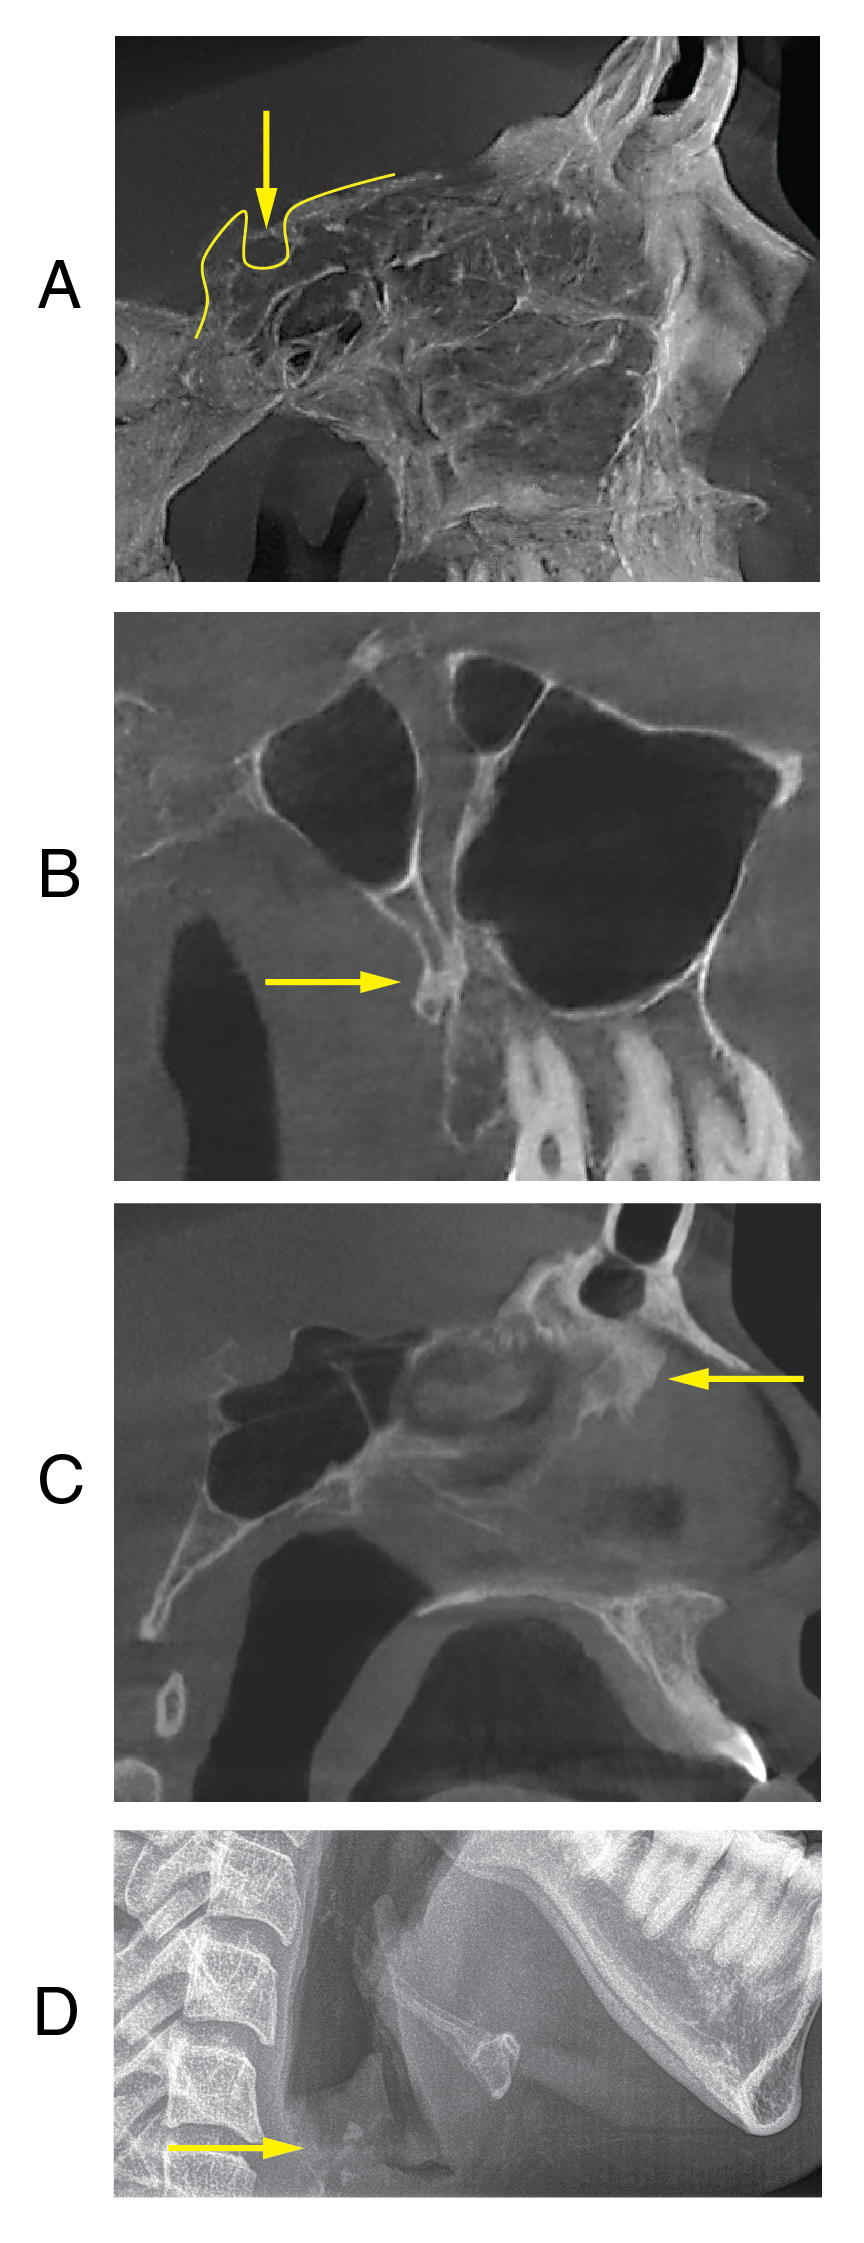

Figure 9: Sporadic Ossification in NM patients. Radiographic images show sporadic ossification in the form of a bridge in the sella turcica (A), fusion of the pterygoid process of the sphenoid bone to the posterior wall of the maxilla in the pterygomaxillary fissure (B), nasal septum (C), and neck in the area of the epiglottis (D).